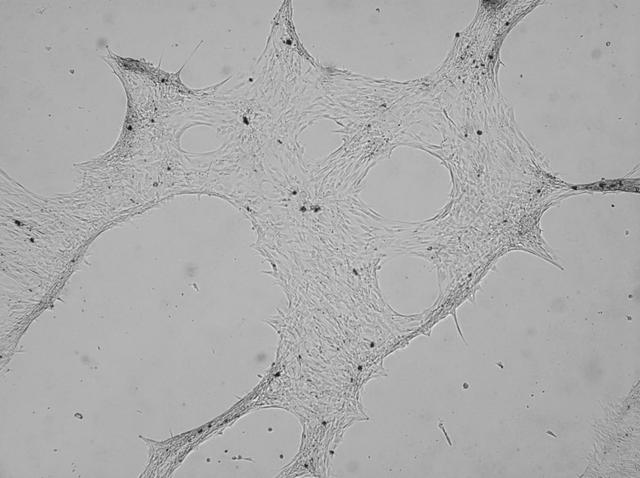

NASA image: PRO Imagery Submittal - READI FP

Image

Aug 11, 2021

PRO Imagery Submittal - READI FP

jsc2021e036650 (8/11/2021) --- A view of Osteogenesis-induced differentiation of human mesenchymal stem cells....

JSC